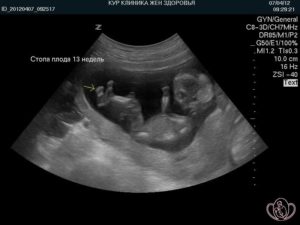

На данном сроке ультразвуковое исследование может показать пол ребенка, наиболее точные сроки беременности (по копчико-теменному размеру плода), а так же проконтролировать вес ребенка.

УЗИ на 16 неделе беременности, при помощи сверх мощных аппаратов УЗИ, может показать пол ребенка. Но говорить о точности в 100% пока рано.

Отвечая на вопрос, как выглядит плод на 16 неделе беременности, нам поможет снимок УЗИ. Малыш уже очень много времени проводит бодрствуя. И сейчас, делая УЗИ, вы можете застать ребеночка, когда он переворачивается, гримасничает или сосет пальчик.

На экране УЗИ можно с легкостью отличить позвоночник и ребра, а так же межреберные пространства. В грудине – черная точка, это 4х камерное сердце, которые уже выполняет свою работу и перекачивает кровь, в размере 23 л за день.

Хорошо различима черточка – диафрагма, которая делит брюшину и грудную клетку. Воздушными полупрозрачными облачками, в ней располагаются легкие – они пока бездействуют.

Сводная таблица беременности: Ваша неделя беременности: 16 Вес: 76-94 г Рост: 109-119 мм Фото плода на 16 неделе беременности: